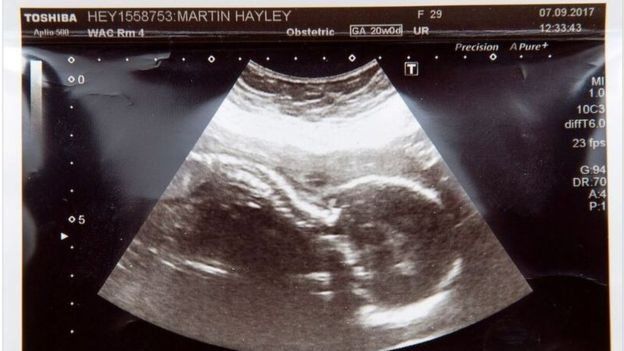

Женщина узнала, что малышка рискует умереть при родах на 20 неделе беременности, потому как у ее ребенка редкое врожденное заболевание - двусторонняя агенезия почек.

Во время утренней передачи This Morning на британском телеканале ITV, 30-летняя Хейли сказала, что они с мужем решили пожертвовать сердечные клапаны своей дочери.